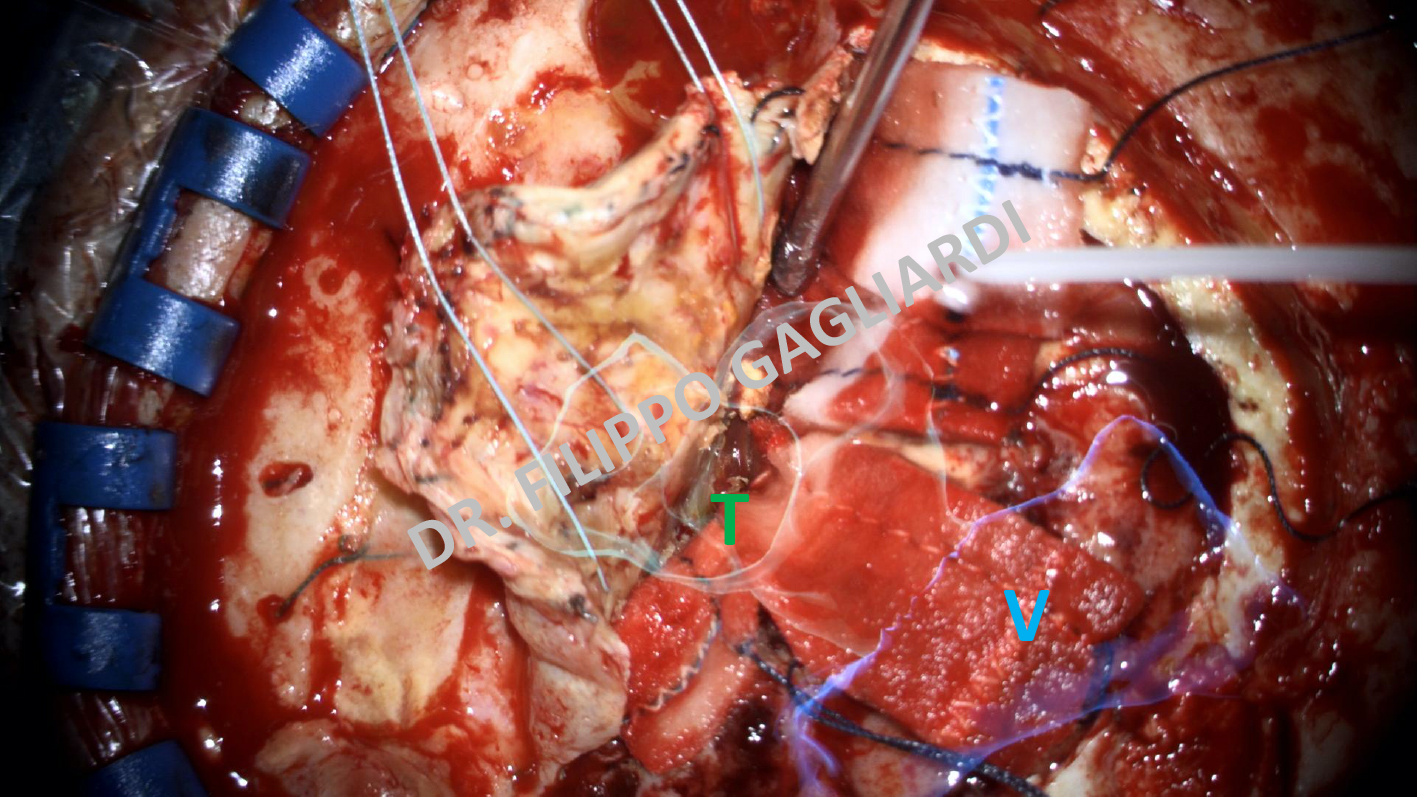

Le immagini di risonanza acquisite pre-operatoriamente vengono ricostruite da software di ultima generazione nelle 3 dimensioni selezionando le strutture di interesse (ROIs ovvero Regions Of Interest). Queste immagini ricostruite vengono superimposte alle immagini visualizzate nel microscopio operatorio in tempo reale durante la chirurgia, per definire l’esatta posizione della malattia rispetto alle strutture anatomiche critiche attorno ad essa, che devono essere risparmiate. Si forma cosi una fusione di immagini reali e ricostruite superimposte, che aiuta il chirurgo ad aumentare la precisione dell’orientamento e della tecnica chirurgica. Pochi centri al mondo, il San Raffaele è uno di questi, dispongono di questa tecnologia all’avanguardia. In questa immagine, tratta da una delle procedure chirurgiche del Dr. Gagliardi si apprezza la visione, al microscopio operatorio, del campo chirurgico. In trasparenza si vede il tumore (volume in verde) e il ventricolo cerebrale (volume in blu). L’integrazione di questa tecnologia con la neuronavigazione consente al sistema di adattare in ogni istante la posizione delle ricostruzioni digitali con l’anatomia reale, correggendo eventuali errori di posizione.